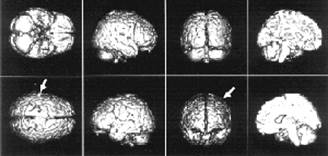

Интересные результаты даёт такой эксперимент. Испытуемому рассказывают одновременно две разные истории: в левое ухо одну, в правое — другую. На верхнем фото изображены разные проекции мозга — стрелками отмечены активизированные зоны, когда внимание сосредоточено на истории, рассказываемой в левое ухо. Внимание испытуемого „переключилось“ на „историю в правом ухе“ (нижнее фото). Можно заметить, что для фиксации внимания на „историю в правом ухе“ требуется гораздо меньшая активность мозга. Это связано с праворукостью большинства людей — обычно они берут телефонную трубку правой рукой и прикладывают её к правому уху. |

Кроме непроизвольного внимания есть ещё и селективное. Это так называемое „внимание на приёме“, когда все вокруг говорят разом, а вы следите только за собеседником, не обращая внимания на неинтересную вам болтовню соседа справа. Во время эксперимента испытуемому рассказывают истории: в одно ухо — одну, в другое — другую. Мы следим за реакцией на историю то в правом ухе, то в левом и видим на экране, как радикально меняется активизация областей мозга. При этом активизация нервных клеток на историю в правом ухе значительно меньше — потому, что большинство людей берут телефонную трубку в правую руку и прикладывают её к правому уху. Им следить за историей в правом ухе проще, нужно меньше напрягаться, мозг возбуждается меньше.